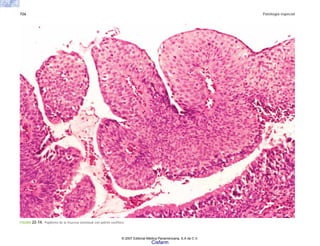

FIGURA 2-13. Histología de las vellosidades articulares en la artritis reumatoide. Hay proliferación de células sinoviales, infiltración inflamatoria y formación de pannus.